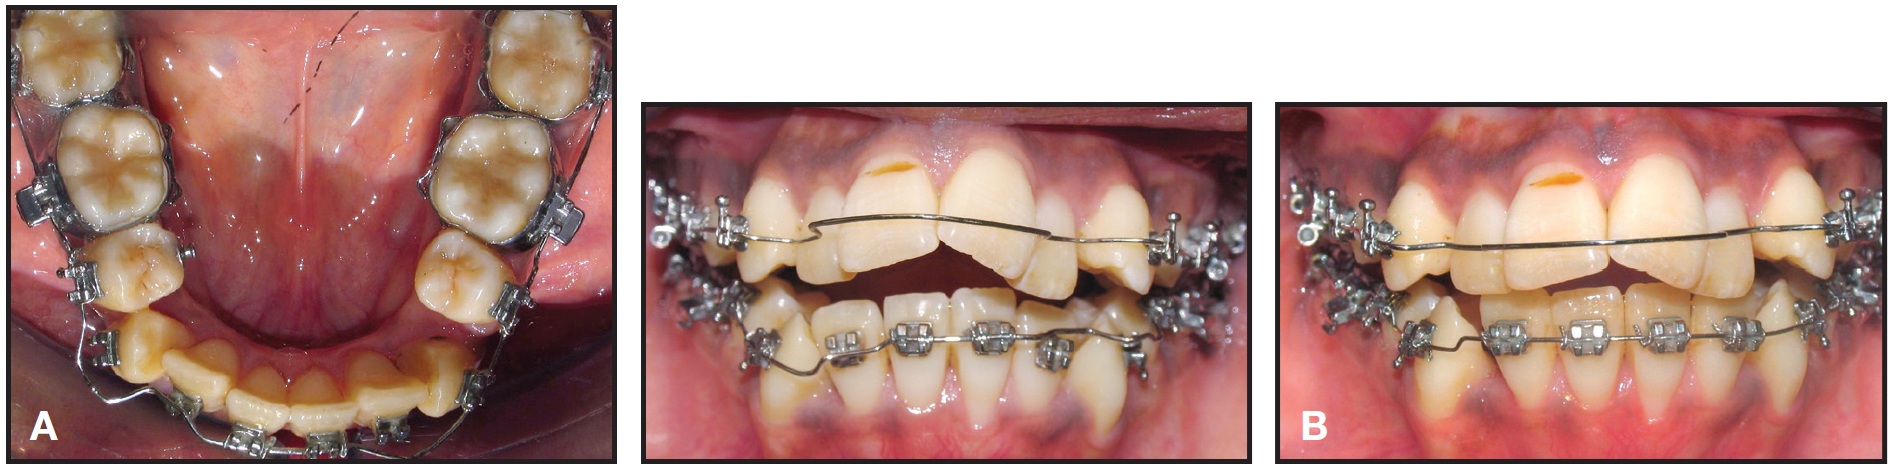

One month later, gradual interproximal reduction was initiated, beginning with the lower left second premolar, to create symmetrical lower premolars. While the upper and lower canines were being distalized, bite closure occurred due to space opening for the upper incisors (Fig. 3).

Fig. 3 After four (A) and seven (B) months of treatment.